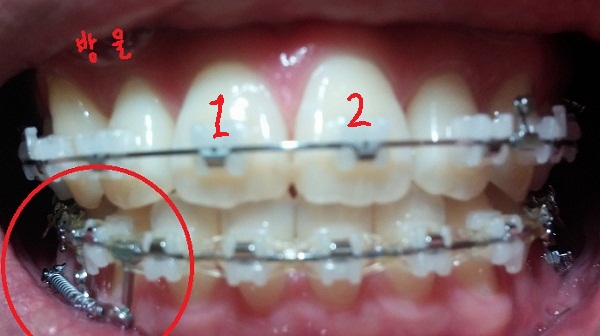

-중심선 99% 맞은 상태!!

-일회용 고무줄로 치아를 다물 때, 뜨는 공간이 없게

상악 송곳니와 하악 송곳니를 당기는 중!!

[정면]

[고무줄 정면]